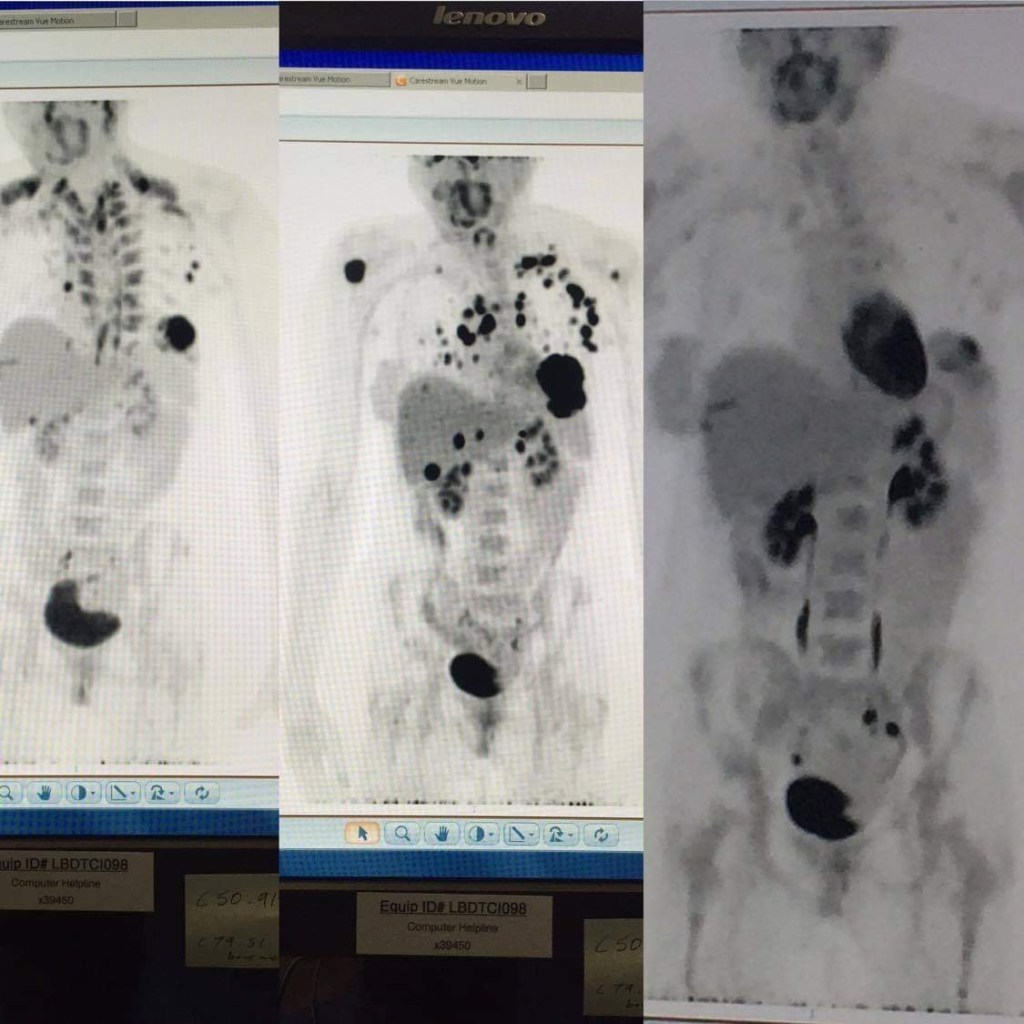

“I keep it as a reminder that that’s what breast cancer looks like. It’s not pretty. It’s not pink. It’s fucking scary”

Zionna referring to her sisters scans of metastatic breast cancer.